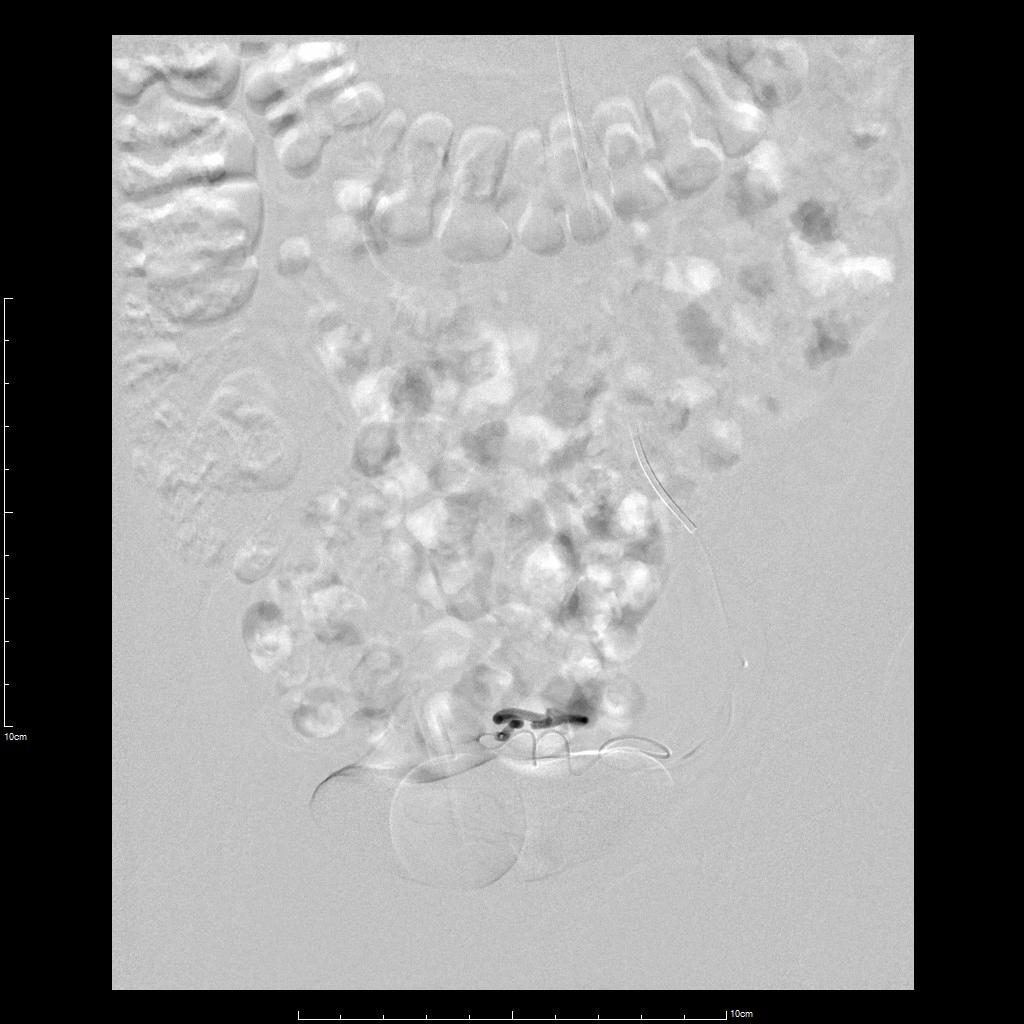

- 超选择插管左侧子宫动脉病灶供血动脉造影+栓塞治疗。

- 术后桡动脉压迫止血6小时,患者术后无需长时间卧床、下肢制动,舒适度明显提高,促进术后快速康复。